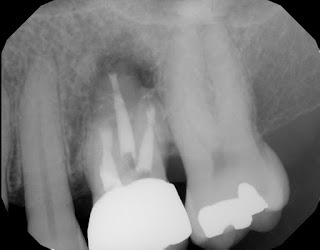

Root resection of all three roots using a buccal approach